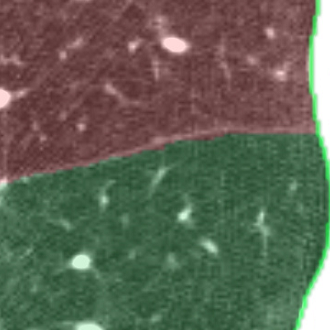

We applied the described segmentation pipeline to the 14 testing datasets which were not used for training and validation. Segmentation including postprocessing takes less than 6 seconds for a case. We compared our method to two other approaches: 1. a non-deep-learning-based automatic method [Lassen et al.(2013)Lassen, van Rikxoort, Schmidt, Kerkstra, van Ginneken, and Kuhnigk] 2. the same u-net as proposed but without weighting. The mean distance from the visible fissure improved to 1.46 mm (without weighting: 2.08 mm). See Figure 2 for plots and Figure 3 for screenshots.

We trained a 3D u-net for a lung lobe segmentation task and showed that emphasizing the lobar boundaries in the loss function improved the segmentation results (see Figure 2 and 3). The segmentation quality is comparable to the method proposed in [Lassen et al.(2013)Lassen, van Rikxoort, Schmidt, Kerkstra, van Ginneken, and Kuhnigk] and even slightly better for the left lobes. This study was performed on a small amount of data. In future work, we plan to train with the same architecture on a much larger database including a wide range of pathologies and performing an extensive evaluation with participation in the LOLA11 [LOLA11()] challenge.